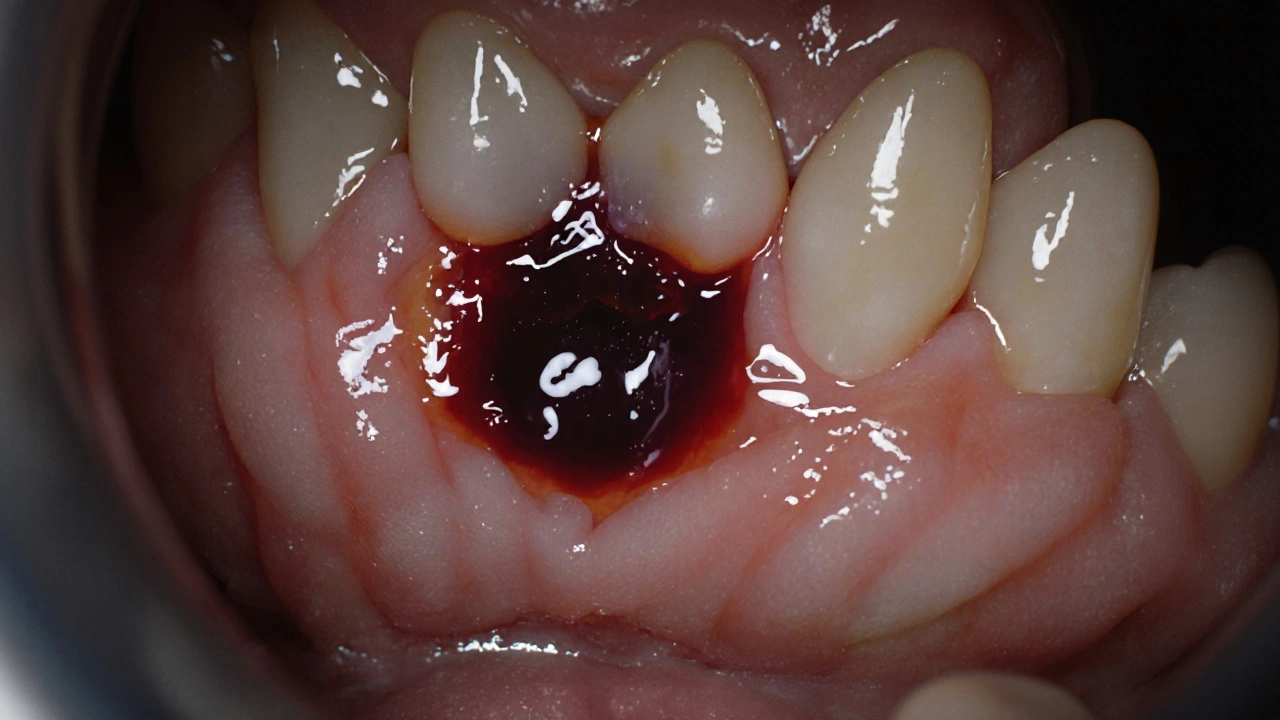

Po vytažení zubu se do místa, kde byl kořen, začne sbírat krev. Ta se do 24 hodin zhroutí do tzv. krevního sraženku - to je váš největší spojenec při hojení. Tento sraženek není jen „krevní špína“. Je to živá tkáň, která chrání kost a nervy pod ní, zabraňuje bakteriím a slouží jako základ pro nové tkáně. Pokud ho ztratíte, zůstane kost odhalená a to znamená bolestnou podmínku, kterou lidé nazývají sušená díra.

První viditelné změny uvidíte už za 3-5 dní. Krevní sraženek se začne měnit - přechází z červené do šedé a pak bílé barvy. To je normální. V té době se začínají tvářit nové tkáně. Přibližně do 7 dní se díra začne zmenšovat, a kůže nad ní se začíná překrývat. To je ten moment, kdy už nevidíte hlubokou „díru“, ale jen malý výběžek nebo jemný výběžek tkáně.